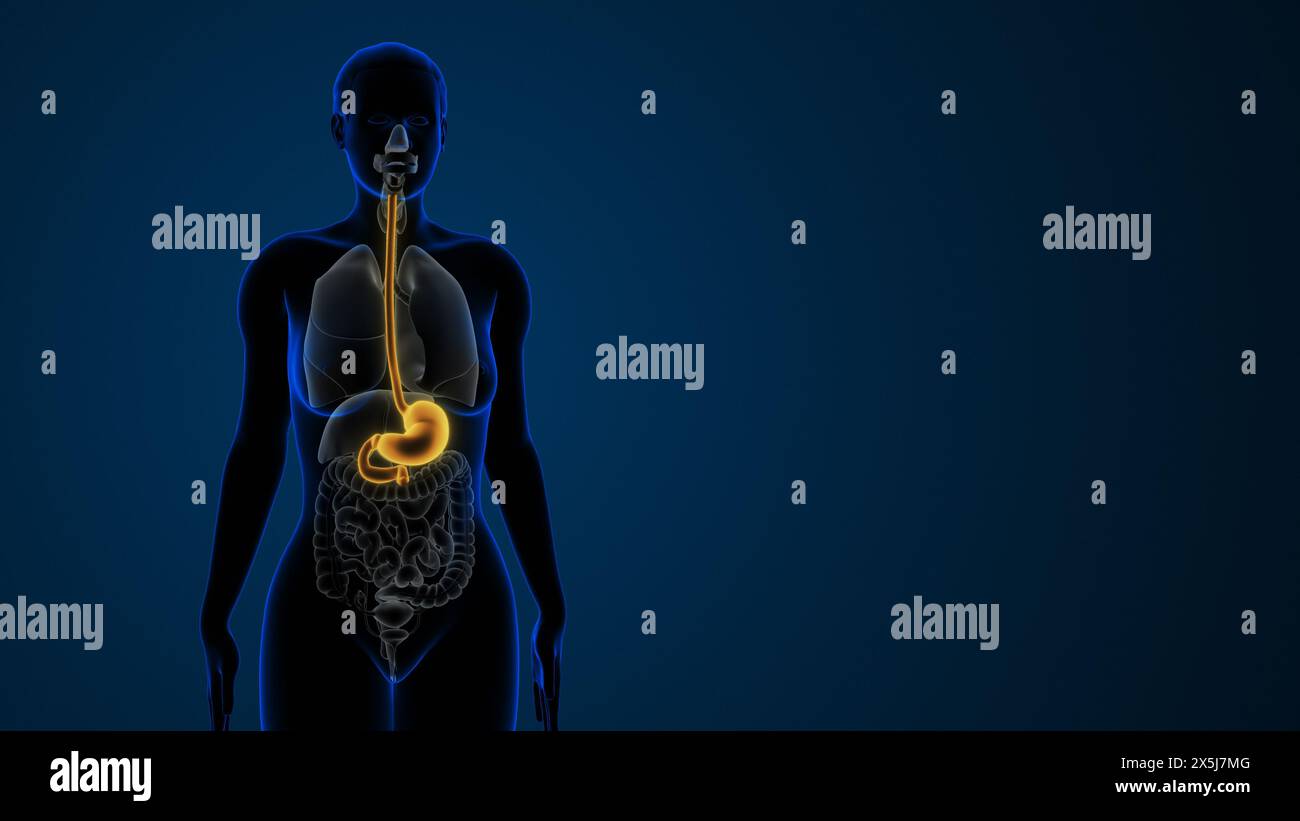

Estomac mis en évidence dans le système digestif féminin Banque D'Imageshttps://www.alamyimages.fr/image-license-details/?v=1https://www.alamyimages.fr/estomac-mis-en-evidence-dans-le-systeme-digestif-feminin-image605837360.html

Estomac mis en évidence dans le système digestif féminin Banque D'Imageshttps://www.alamyimages.fr/image-license-details/?v=1https://www.alamyimages.fr/estomac-mis-en-evidence-dans-le-systeme-digestif-feminin-image605837360.htmlRF2X5J7MG–Estomac mis en évidence dans le système digestif féminin

Estomac mis en évidence dans le système digestif féminin Banque D'Imageshttps://www.alamyimages.fr/image-license-details/?v=1https://www.alamyimages.fr/estomac-mis-en-evidence-dans-le-systeme-digestif-feminin-image605838979.html

Estomac mis en évidence dans le système digestif féminin Banque D'Imageshttps://www.alamyimages.fr/image-license-details/?v=1https://www.alamyimages.fr/estomac-mis-en-evidence-dans-le-systeme-digestif-feminin-image605838979.htmlRF2X5J9PB–Estomac mis en évidence dans le système digestif féminin

Estomac mis en évidence dans le système digestif féminin Banque D'Imageshttps://www.alamyimages.fr/image-license-details/?v=1https://www.alamyimages.fr/estomac-mis-en-evidence-dans-le-systeme-digestif-feminin-image605837554.html

Estomac mis en évidence dans le système digestif féminin Banque D'Imageshttps://www.alamyimages.fr/image-license-details/?v=1https://www.alamyimages.fr/estomac-mis-en-evidence-dans-le-systeme-digestif-feminin-image605837554.htmlRF2X5J7YE–Estomac mis en évidence dans le système digestif féminin